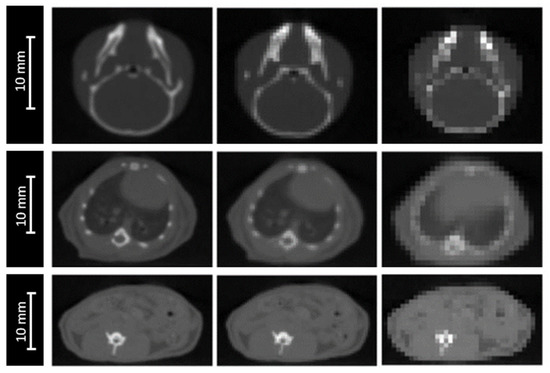

The impact of image resolution was evaluated for brain, lungs and intestine irradiations by degrading the grid size to 0.4 × 0.4 × 0.4 mm3 and 0.8 × 0.8 × 0.8 mm3 (Figure 3), while maintaining the calculation grid size at 0.2 × 0.2 × 0.2 mm3 to prevent the accumulation of sources of uncertainties.

Figure 3.

CBCT of a mouse’s head (top), thorax (middle). and abdomen (bottom) for three different CBCT grid sizes: 0.2 × 0.2 × 0.2 mm3 (left), 0.4 × 0.4 × 0.4 mm3 (middle), and 0.8 × 0.8 × 0.8 mm3 (right).

For the three studied localizations, the CT grid size had no significant impact on the absorbed dose in the plateau. However, the proton range was significantly impacted, with a maximal deviation of ±0.6 mm for the worst spatial resolution (0.8 × 0.8 × 0.8 mm3). The HI98 along the beam axis was not significantly impacted by the degradation of the spatial resolution, excepted from the lungs, for which the HI98 value increased from 0.12 to 0.14, using a spatial resolution of 0.8 × 0.8 × 0.8 mm3. Variations of the HI98 and the Bragg peak position observed for an intermediate spatial resolution of 0.4 × 0.4 × 0.4 mm3 were below the significance thresholds.